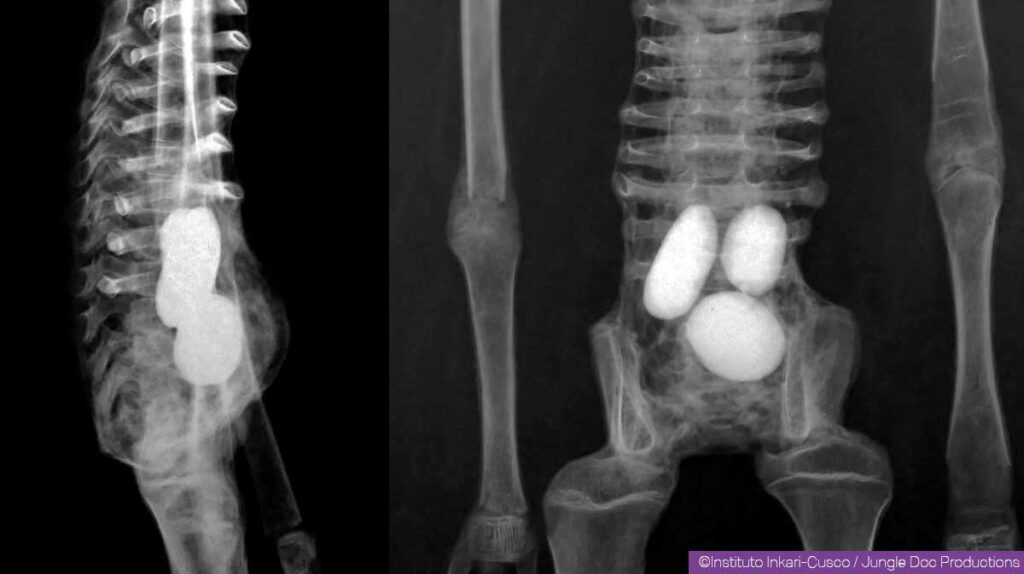

骨の構造を調べると、人間の場合上腕部は橈骨と尺骨、下肢も脛骨と腓骨という二本の骨で構成されているのに対し、このタイプは上腕も下肢も一本の棒のような骨しか持っていない。女性と思われる個体の体内には、卵らしき楕円形の物体が確認されており、その多くに金属片が埋め込まれている。

ジャミンが「ホセフィーナ」を入手したのは2017年4月のことで、身長58.5センチ。下腹部が少し膨らんでおり、X線撮影の結果体内に、卵と思われる3つの楕円形の物体が見つかっている。卵の形は鳥類と異なり、爬虫類のものに似ている。胸には金属板が埋め込まれており、成分を分析したところ銅が85%だという。